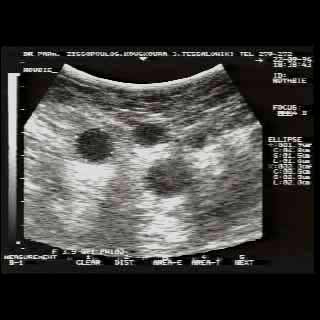

Για την καλλίτερη απόδοση της εξέτασης απαιτείται κεφαλή linear τουλάχιστον 7,5 ΜΗΖ. Ωστόσο και με κεφαλές 3,5 και 5 ΜΗΖ μπορεί κανείς να έχει καλά αποτελέσματα.

Οι απεικονίσεις των περιστατικών που επιδεικνύονται παρακάτω, έγιναν με κυρτές κεφαλές 3,5 και 5 ΜΗΖ, προκειμένου να φανεί, ότι και με τον εξοπλισμό αυτό, που σιγά-σιγά διαθέτουν όλο και περισσότερα ιατρεία, είμαστε σε θέση να έχουμε ικανοποιητικά αποτελέσματα.

Oι τελευταίες 4 απεικονίσεις έγιναν με ειδικό για μαστό ηχοβολέα linear, εναλλασσομένης συχνότητος 7,5-10ΜΗΖ.